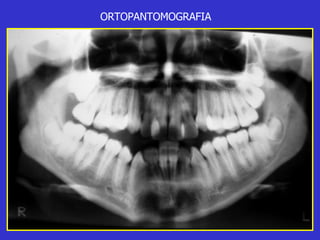

Este documento describe las diferentes proyecciones radiográficas utilizadas para examinar los senos paranasales, incluyendo las proyecciones básicas de Caldwell, Waters lateral y las proyecciones especiales como Hirtz y Waters mentonasal. También describe las diferentes estructuras anatómicas que componen el complejo ostiomeatal anterior y posterior de los senos paranasales.